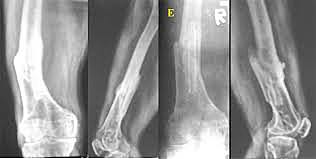

• Kuntscher

Kuntscher